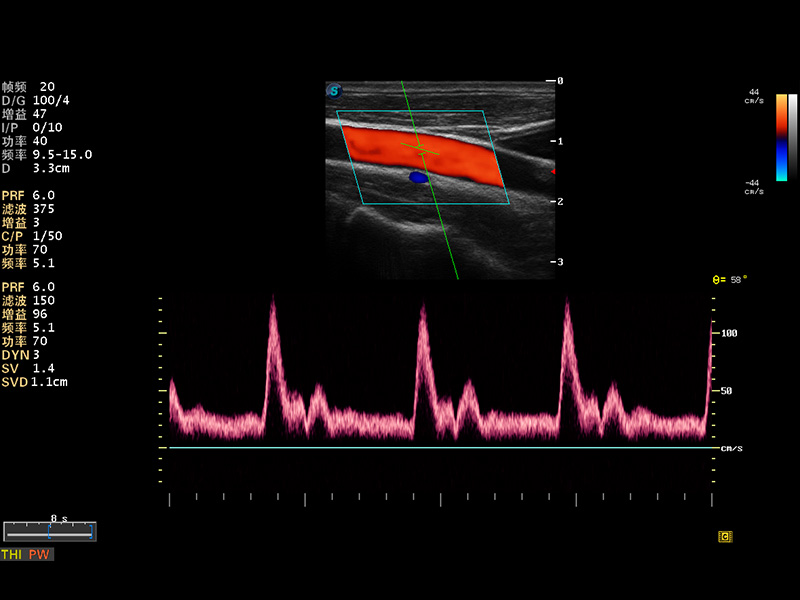

S8 EXP便携式彩色多普勒超声诊断仪是DB中国旗舰官方网站研发的高端全身应用型便携彩超。高通道的VIS平台融合可视化(Visual)、智能化(Intelligent)和人性化(Smart)的特点,配以DB中国旗舰官方网站自主研发生产的探头大家族,使您能够快速、准确的获得病人信息,提高工作效率的同时减轻疲劳。

成像技术

多波束形成器

μ-Scan微米成像

谐波成像

实时宽景成像

空间复合成像

3D/4D成像